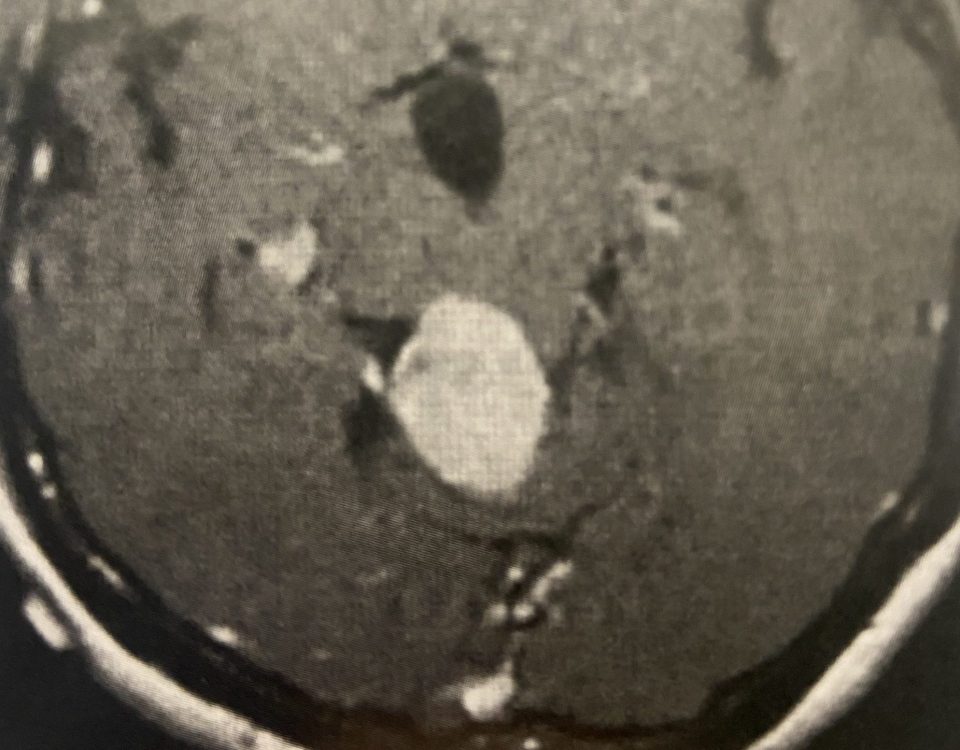

This is a 57-year-old woman with new onset memory problems and gait difficulty. MRI demonstrated a 3 cm tumor in the pineal region, most consistent with […]